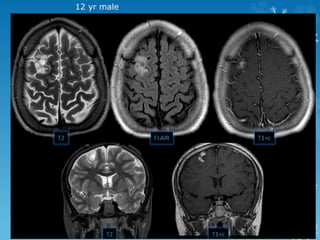

12 yr male